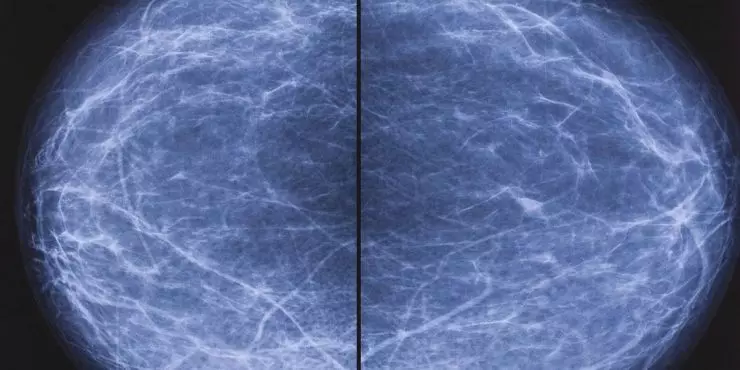

Mammograms and Breast Density

Dense breast tissue is common and can make mammograms harder to interpret. If your report mentions density, your clinician may discuss 3D mammography and whether supplemental screening (such as ultrasound or MRI based on risk) makes sense for you.